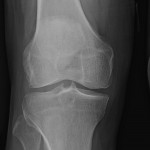

Case Study, Knee #Osteoarthritis, #AAOS Evidence Based Practice Guidelines

Popular answer may not imply right answer, Follow our twitter handle for the right answer, www.twitter.com/drhiteshg